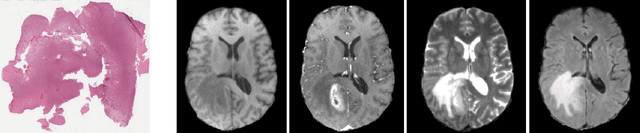

Abstract:Cancer is a complex disease that provides various types of information depending on the scale of observation. While most tumor diagnostics are performed by observing histopathological slides, radiology images should yield additional knowledge towards the efficacy of cancer diagnostics. This work investigates a deep learning method combining whole slide images and magnetic resonance images to classify tumors. Experiments are prospectively conducted on the 2020 Computational Precision Medicine challenge, in a 3-classes unbalanced classification task. We report cross-validation (resp. validation) balanced-accuracy, kappa and f1 of 0.913, 0.897 and 0.951 (resp. 0.91, 0.90 and 0.94). The complete code of the method is open-source at XXXX. Those include histopathological data pre-processing, and can therefore be used off-the-shelf for other histopathological and/or radiological classification.